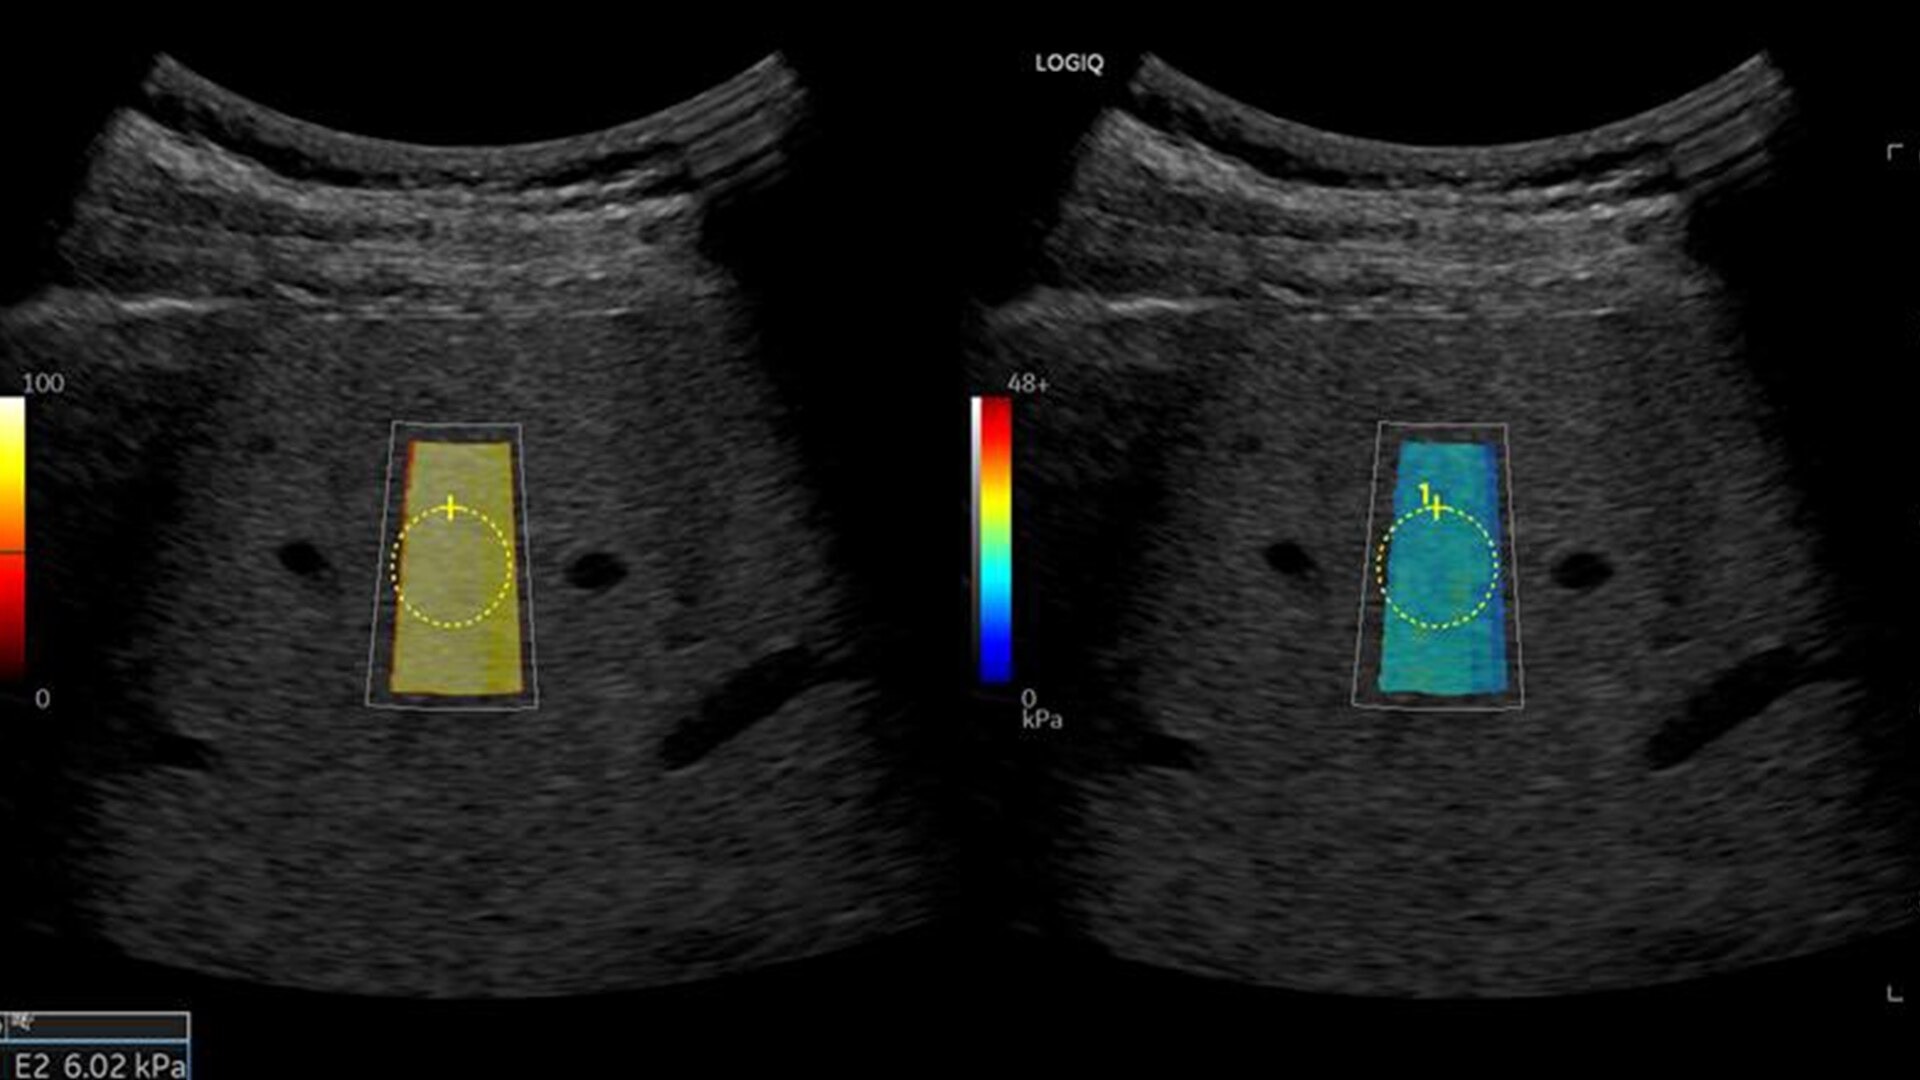

• 2D shear wave elastography with quality map provides quantitative insight into tissue elasticity—helping you assess different structures with confidence

• Hepatic Assistant: Combines 2D shear wave elastography and UGFF in a single workflow